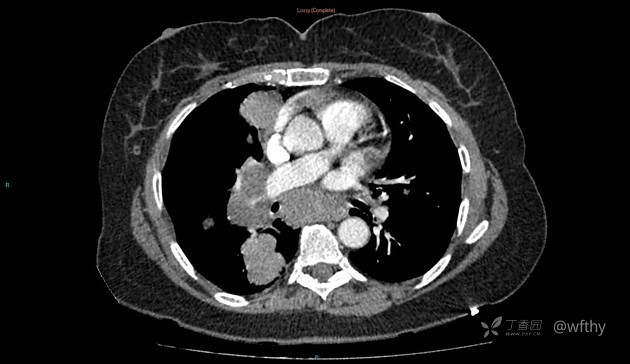

病例女65,头部肿块